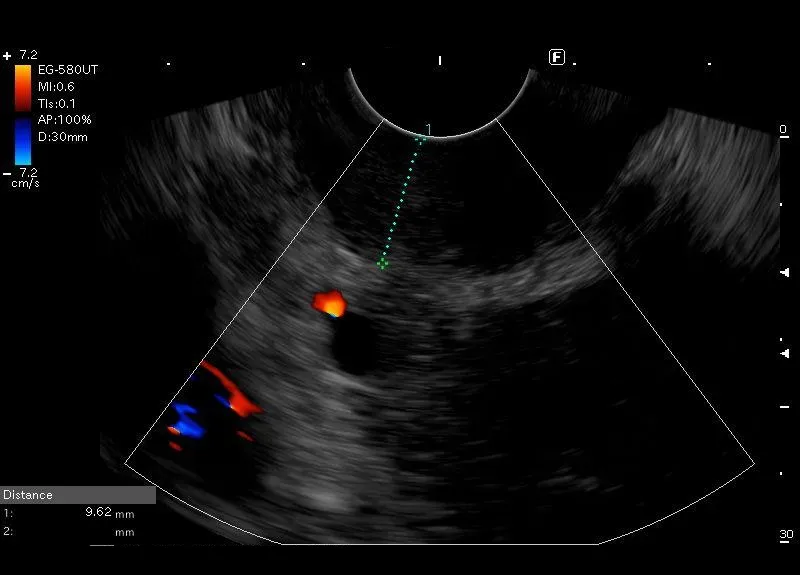

Pogrubienie ściany dwunastnicy do około 12-15 mm z obecnością

śródściennych torbieli - w wybranym przypadku odpowiada zapaleniu bruzdy.